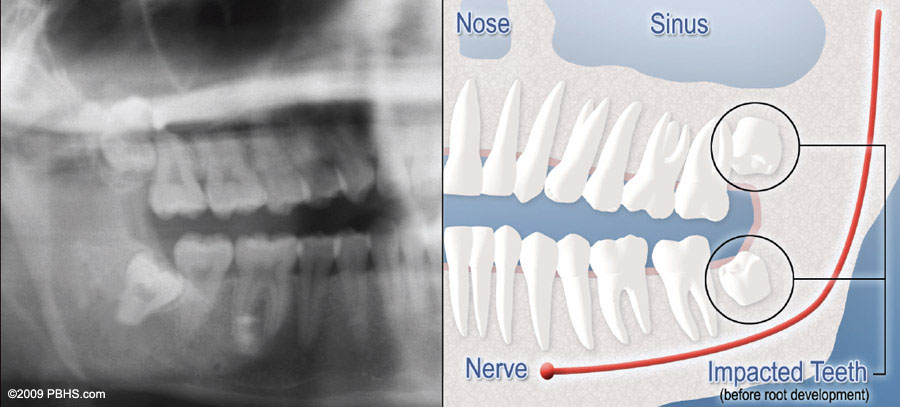

wisdom tooth soft tissue impaction

Partial Bony Impacted Wisdom Teeth

There is enough space to allow the wisdom tooth to partially erupt. However, the tooth cannot function properly in the chewing process, and creates cleaning problems, among others.